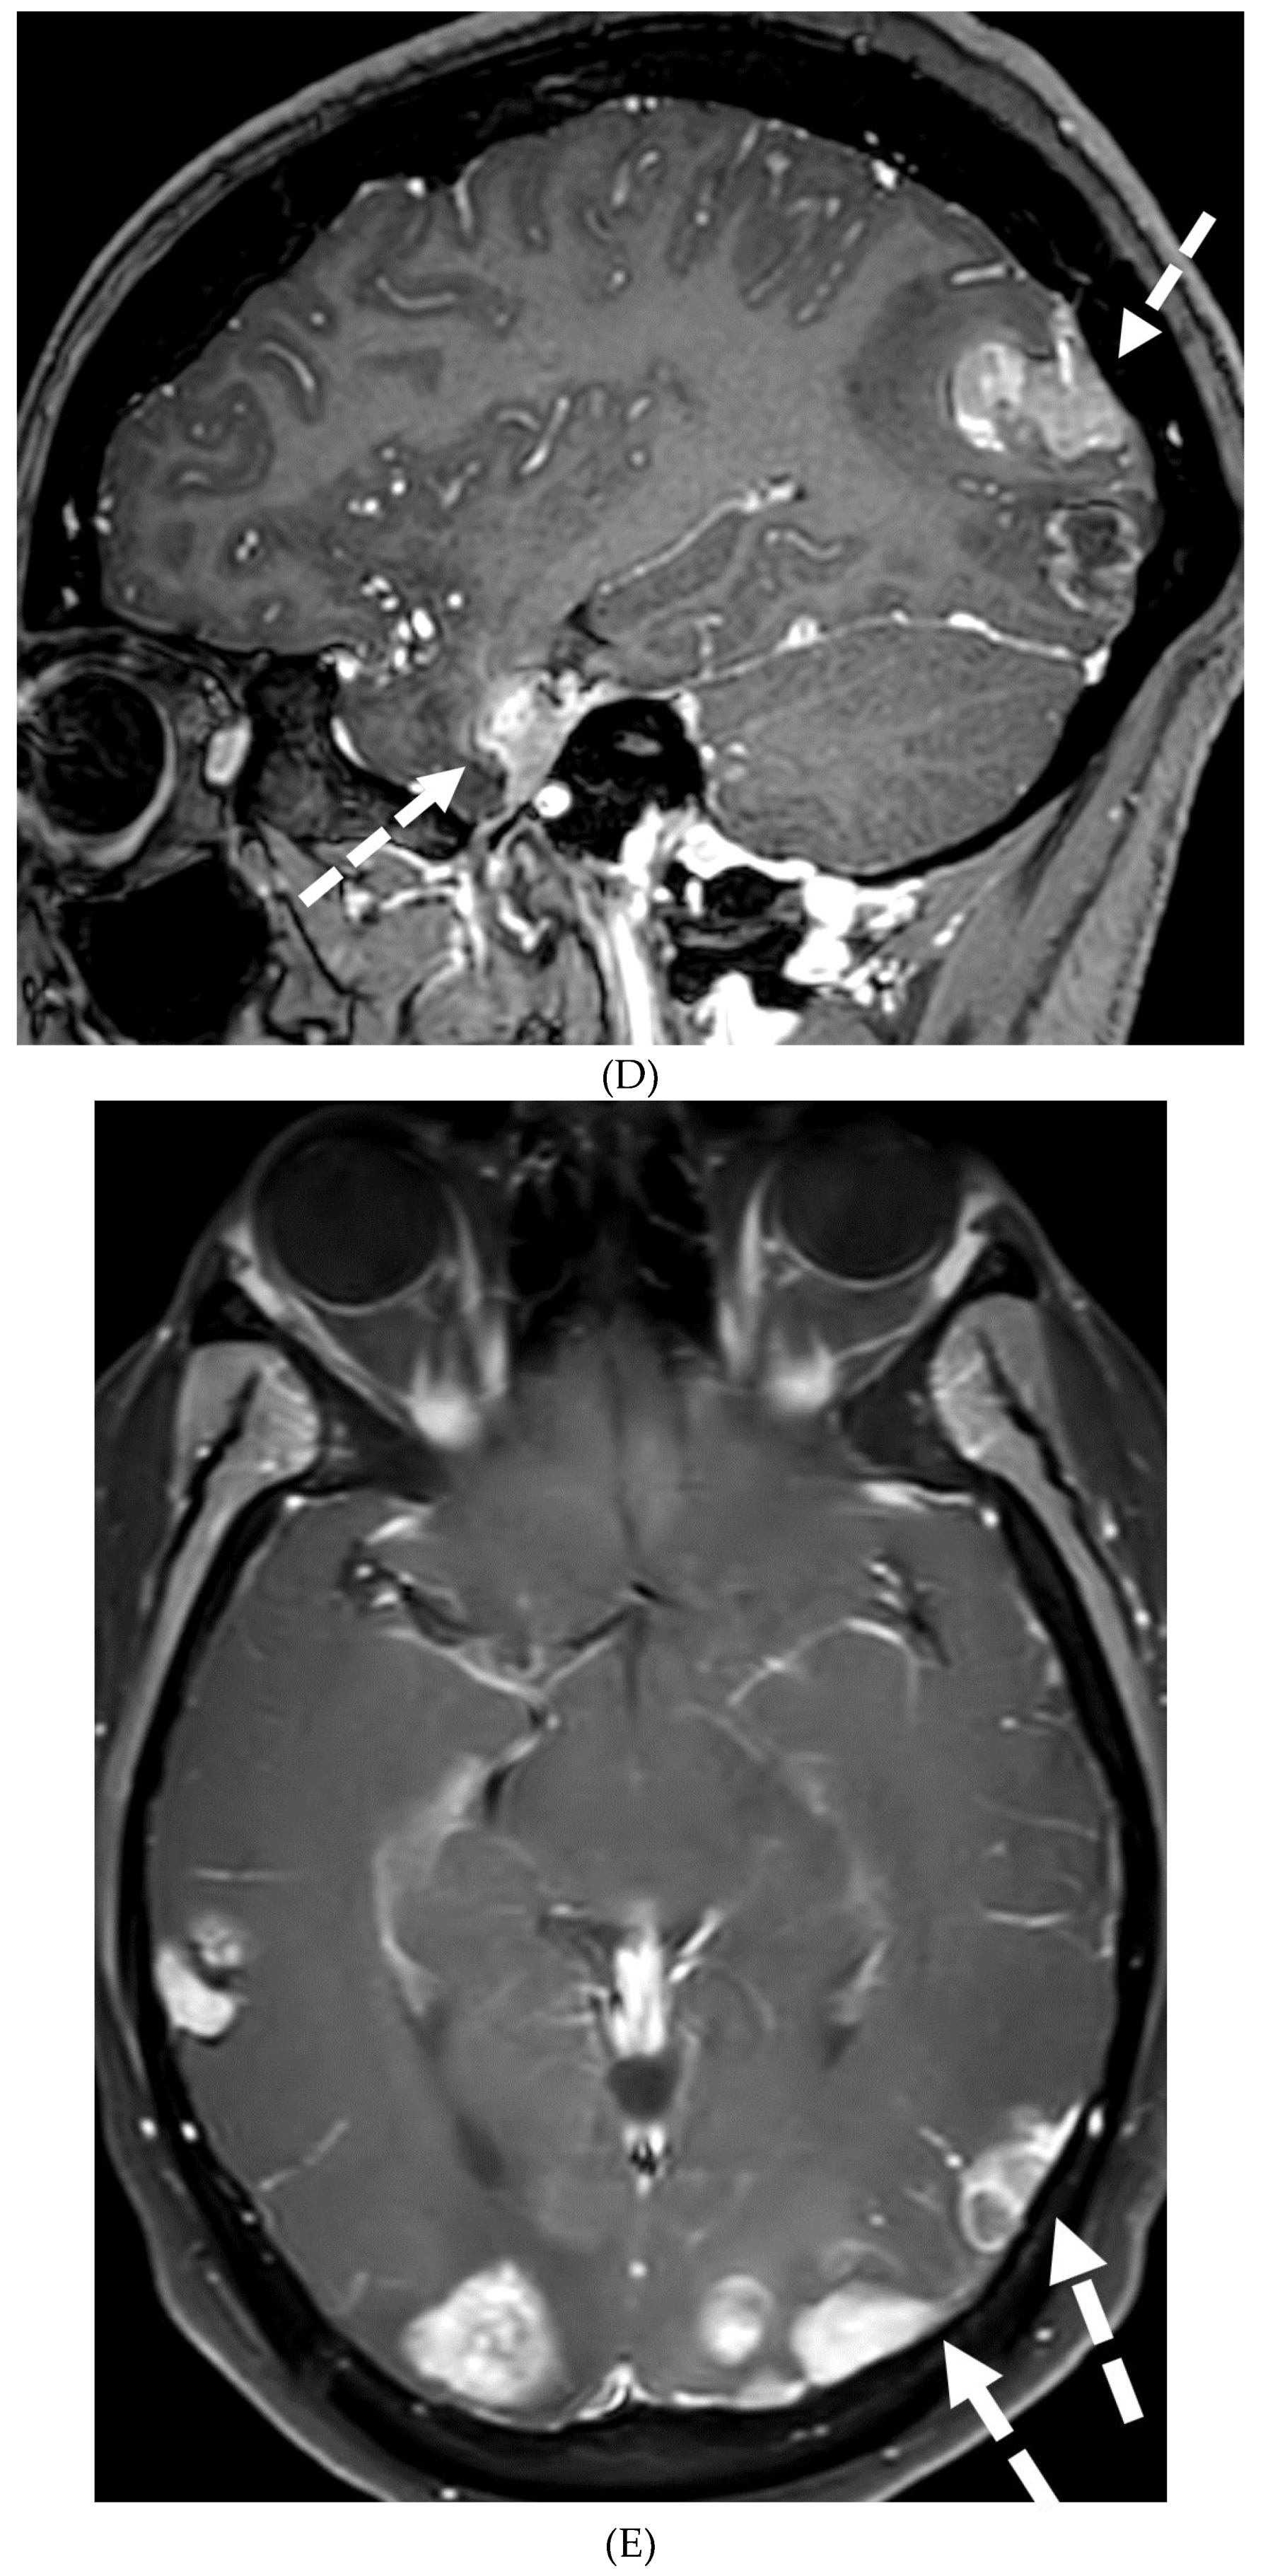

SYSTEMIC MENINGEAL METASTASES (SMM)